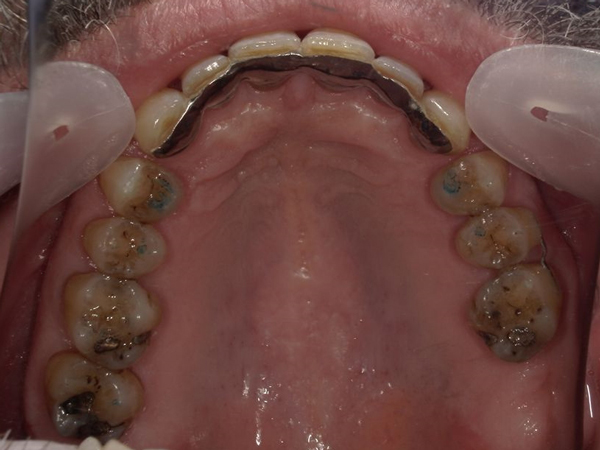

Arcade mandibulaire avant traitement orthodontique, séquelles de maladie parodontale

Après traitement orthodontique et réalisation d’une attelle fibrée (courtoisie Dr Patrick Fournier)